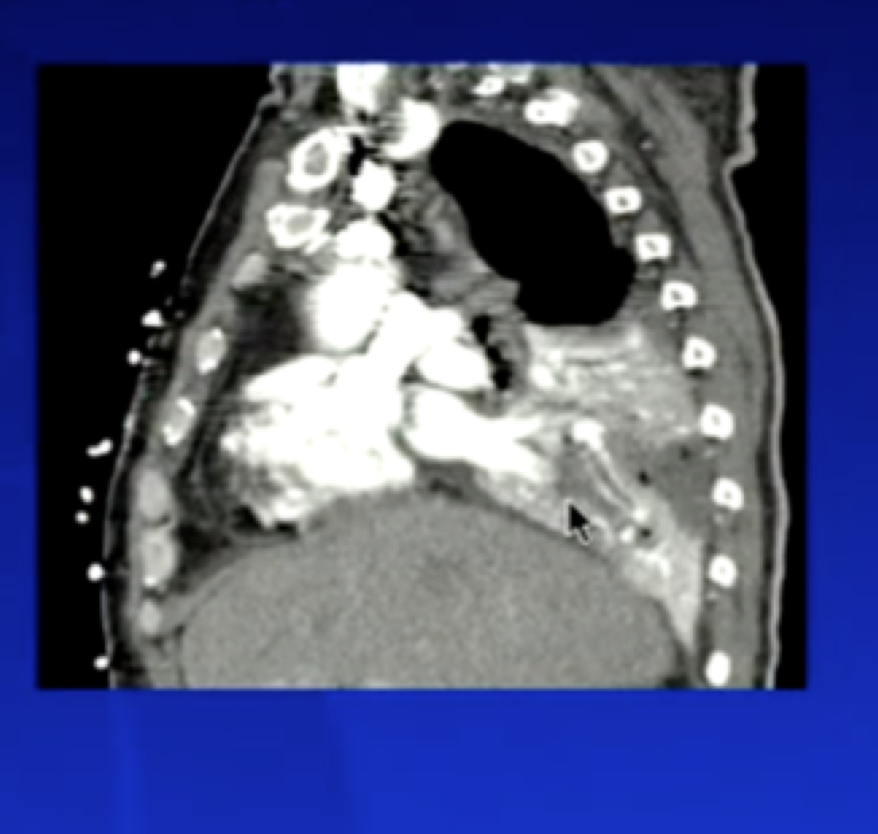

Saddle Embolism: When it goes over bifurcation of pulmonary artery